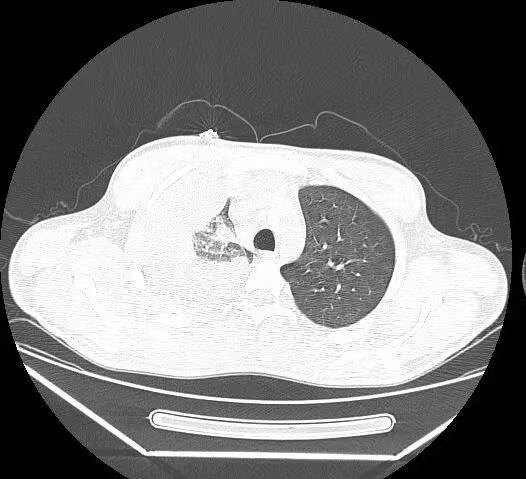

胸部+上腹部增强CT:2023.12.04我院门诊肺部CT示:1.左肺上叶结片影;右肺上叶及右肺门结块,右肺门形态增大,右肺下叶部分支气管截断,多考虑肿瘤性病变,请结合临床病史及对比前片。2.右侧胸腔积液;伴右下肺膨胀不全。3.扫及肝脏囊性灶;胆囊结石。

1、胸水引流和灌注化疗:于2023.12.04 行右侧胸腔积液穿刺引流术,引流出约1500m1淡红色胸水,送检细胞学可找到肿瘤细胞。于12.08 、12.15行2次顺铂(40mg)胸腔灌注化疗,过程顺利,未诉不适。复查胸部CT提示胸水消失。

OoCNxjw6Pe2NhnUiFbeWjYFJJF3cHziA.png

CT.jpg1.png2.png3.png